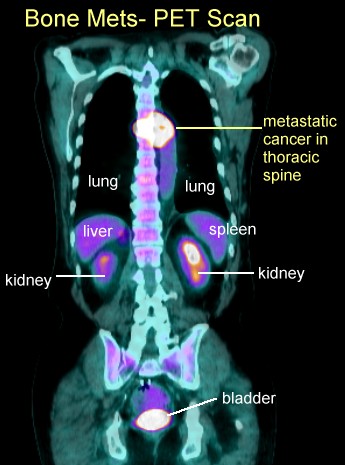

PET Scans of Bone Metastases

PET scans may show these lesions best (go here , here, here, here, here, here, here , here , here , here , here , here , here and here) even better than CT scans (go here , here, here and here) and better than MRI (here). PET scans also show the response to radiation (go here). PET is helpful for hard to see areas like the ribs or scapula. PET's may be best for

osteolytic lesions and bone scans best for blastic metastases (go

here). |